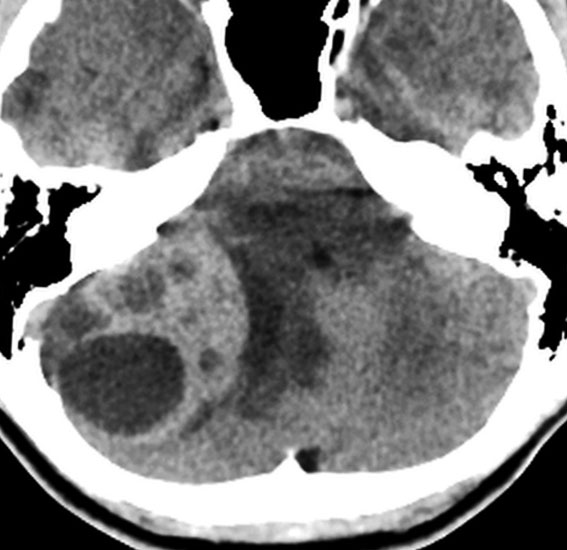

- CTでは石灰化がみられることがあります

- CTでは小脳より白っぽい灰色(高密度)に写ります

この例は,小脳半球にできたものです。のう胞(水たまり)を形成しています。髄芽腫の大きな特徴は,造影剤を入れないCT(左側)で腫瘍が少し白く見えることです(灰白質より高密度といいます)。細胞密度が高いので高密度になります。この例はclassic medulloblastomaですが,MIB-1は45%に達するもので,急激な腫瘍発育を示します。